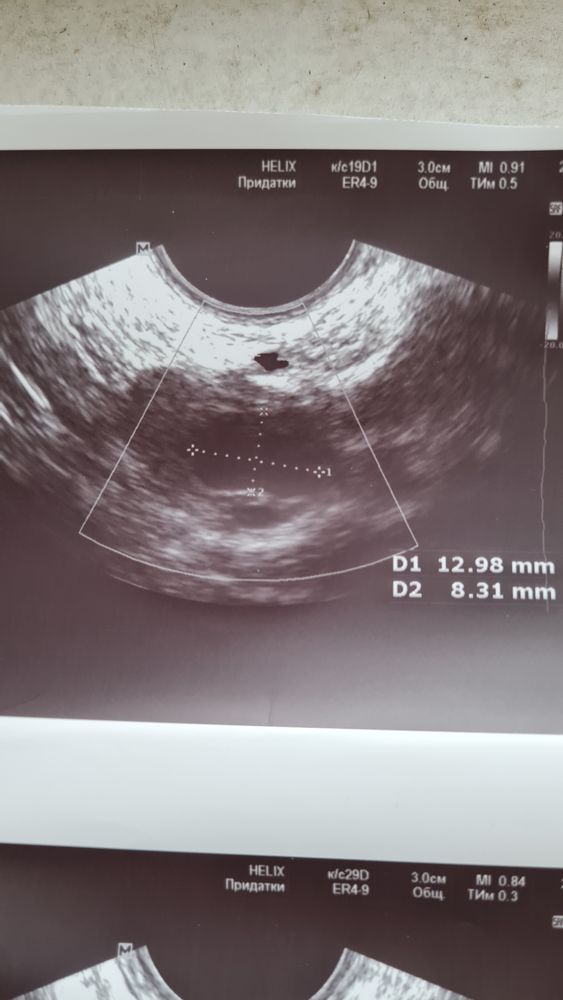

ФолликулометрияДевочки, сегодня 11 дпо. Сходила на УЗИ, так как цикл обычно 28 дней, а сегодня уже 32 день. По ощущениям О была на 21 день.😒 Я думала сейчас найдут ЖТ, а врач говорит, что это фолликул не лопнул😭 Посмотрите УЗИ и фото, прошу, кто в этом разбирается. БТ 36,9.

Врач вам все верно описал. Или оболочка толстая была у фолика, или просто чего-то не хватило. Овули не было, к сожалению

Фолликул действительно не лопнул - он лютеинизировался, сдулся. Так бывает. Но если в каждом цикле так, то нужно колоть ХГЧ, чтобы лопались.